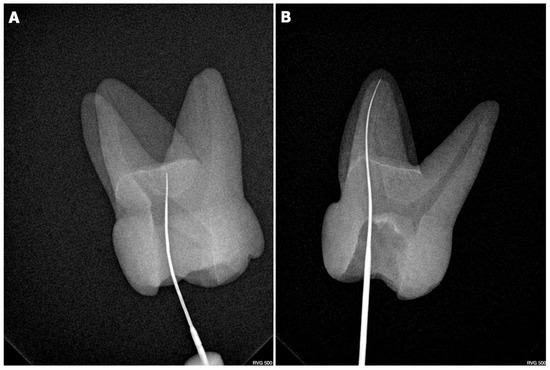

Background: Dens invaginatus is a rare developmental tooth anomaly that can occur in permanent, primary, and supernumerary teeth, with a tendency to affect the maxillary second incisors. It develops during odontogenesis due to the invagination of the enamel organ into the dental papilla. [...] Read more.

Background: Dens invaginatus is a rare developmental tooth anomaly that can occur in permanent, primary, and supernumerary teeth, with a tendency to affect the maxillary second incisors. It develops during odontogenesis due to the invagination of the enamel organ into the dental papilla. Methods: This study describes the endodontic management of a 24-year-old patient with a type IIIb invaginated tooth in the mandibular second molar. Clinical examination revealed no response to thermal and electrical stimuli, no response to vertical and horizontal percussion, and no pathological mobility. The depth of the gingival pocket was 8 mm. Root canal therapy was performed over three sessions. The patient remained asymptomatic during the treatment and follow-up visits. Results: Radiographs at 4-, 6-, and 9-month post-treatment showed healing of the periapical lesion. Conclusions: Due to the complex canal anatomy of invaginated teeth, confirming the diagnosis with cone-beam computed tomography (CBCT) is essential. Treating invaginated teeth presents significant challenges for clinicians, requiring a thorough understanding of the dental anatomical variability, advanced manual skills, and the use of specialized equipment. Full article

Show Figures

Figure 1